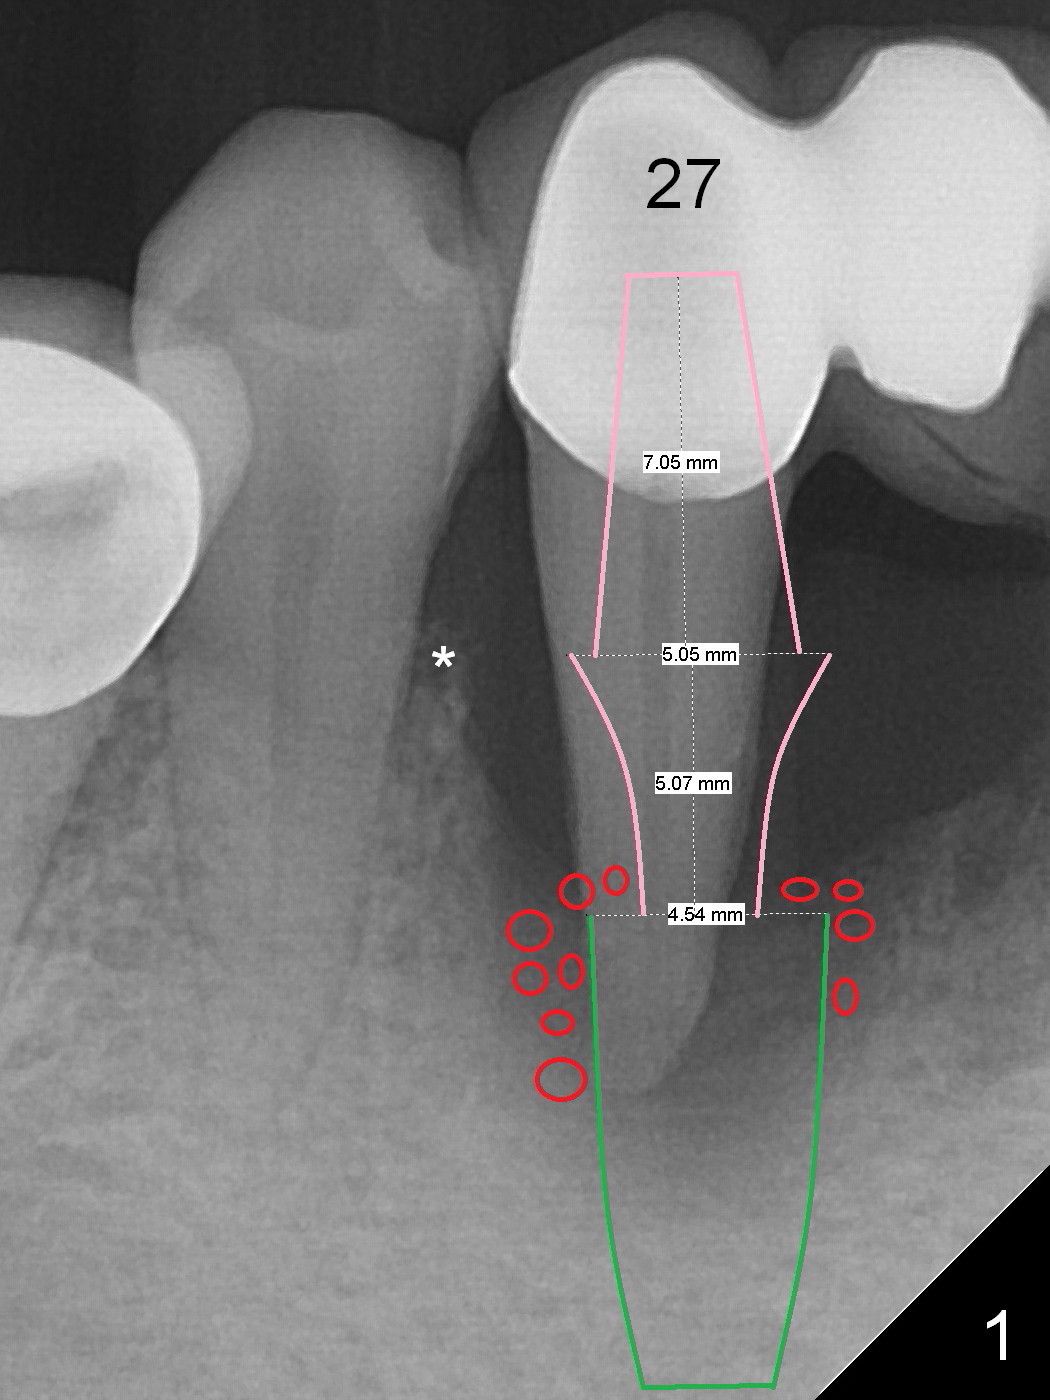

A 57-year-old woman has a 20-year-old loose FPD (fixed partial denture, Fig.1-3). Upon Alginate impression for stent, the 6-unit FPD was dislodged with the exfoliated abutment at #27. After removal of calculus from the root of #27, the FPD was placed in situ and temporarily cemented to #22 abutment. When the patient returns, remove the FPD, treat the socket of #27 with Clindamycin, place implants at #23, 25 and 27 and fabricate a 6-unit provisional FPD. At definitive stage of restoration, fabricate a 4-unit FPD at #24-26 and a single unit at #27. Since bone loss is more severe mesiobuccally at #27 (Fig.1), place an implant as lingual as possible, but slightly more mesially. If the defect is so severe that the implant (green) has to be placed deep, the abutment margin with the longest cuff (5 mm, pink) is less likely to contact the distal crest (*). Crown margin (i.e., abutment margin of an implant) should be 2 mm more coronal to the crest normally. The condition that does not meet the requirement is called violation of biologic width, associated with periodontitis or periimplantitis.